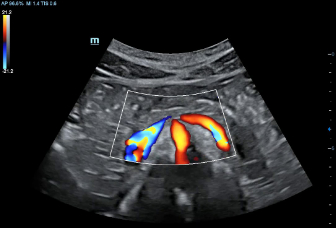

DC-70 Exp

–Ш–љ—Б—В—А—Г–Љ–µ–љ—В –і–ї—П –≤—Л—Б–Њ–Ї–Њ–Ї–∞—З–µ—Б—В–≤–µ–љ–љ–Њ–є –і–Є–∞–≥–љ–Њ—Б—В–Є–Ї–Є

X-Insight вАУ —Н—В–Њ –Њ—В–ї–Є—З–љ–Њ–µ —А–µ—И–µ–љ–Є–µ –і–ї—П –Њ–њ—А–µ–і–µ–ї–µ–љ–Є—П –љ–Њ–≤—Л—Е –≤–Њ–Ј–Љ–Њ–ґ–љ–Њ—Б—В–µ–є.

–°–Њ–≤–Љ–µ—Б—В–љ–Њ —Б —Б–Њ–≤—А–µ–Љ–µ–љ–љ—Л–Љ–Є —Г–ї—М—В—А–∞–Ј–≤—Г–Ї–Њ–≤—Л–Љ–Є —В–µ—Е–љ–Њ–ї–Њ–≥–Є—П–Љ–Є –љ–Њ–≤–Њ–µ —А–µ—И–µ–љ–Є–µ –Њ—В Mindray –њ—А–µ–Њ–±—А–∞–Ј—Г–µ—В –∞–Ї—В—Г–∞–ї—М–љ—Л–µ –Ј–∞–і–∞—З–Є –Ї–ї–Є–µ–љ—В–Њ–≤ –≤ –Ї–ї–Є–љ–Є—З–µ—Б–Ї–Є–µ –њ–Њ—В—А–µ–±–љ–Њ—Б—В–Є.

–°–Є—Б—В–µ–Љ–∞ DC-70 Exp —Б X-Insight –њ–Њ–Љ–Њ–≥–∞–µ—В —Г–њ—А–∞–≤–ї—П—В—М –њ–Њ–≤—Б–µ–і–љ–µ–≤–љ–Њ–є –Ї–ї–Є–љ–Є—З–µ—Б–Ї–Њ–є –њ—А–∞–Ї—В–Є–Ї–Њ–є —Б –ї–µ–≥–Ї–Њ—Б—В—М—О –Є —Г–≤–µ—А–µ–љ–љ–Њ—Б—В—М—О.

–Ю—Б–љ–Њ–≤—Л–≤–∞—П—Б—М –љ–∞ –≥–ї—Г–±–Њ–Ї–Њ–Љ –њ–Њ–љ–Є–Љ–∞–љ–Є–Є –њ–Њ—В—А–µ–±–љ–Њ—Б—В–µ–є –Ї–ї–Є–µ–љ—В–Њ–≤, –Ї–Њ–Љ–њ–∞–љ–Є—П Mindray —А–∞–Ј—А–∞–±–Њ—В–∞–ї–∞ —Б–Є—Б—В–µ–Љ—Г DC-70 Exp —Б X-Insight, —З—В–Њ–±—Л –Њ–±–µ—Б–њ–µ—З–Є—В—М eXpress Clarity, eXceptional Intelligence, eXceeding Experience.